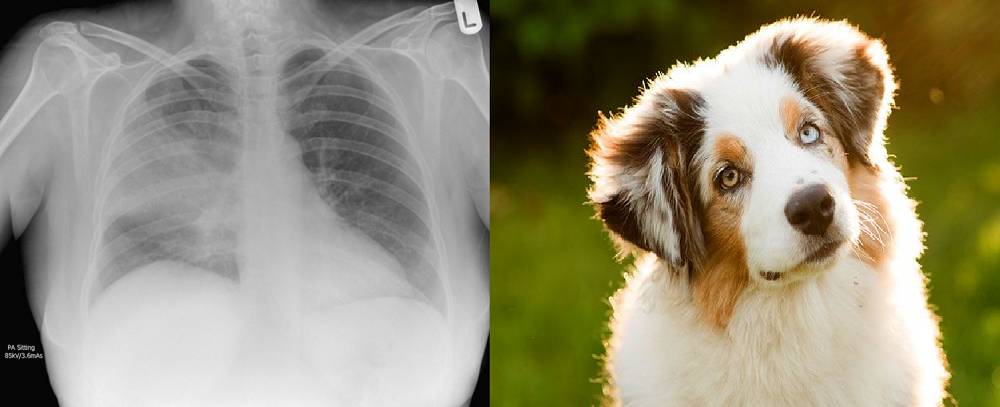

我基本同意 Jeremy 的观点,虽然这依赖于任务类型和噪声类型。随机噪声可以作为不错的正则化项,甚至还可以在某些设置中提升性能(这种技术被称为标签平滑或软标签)。结构化噪声不一样,它添加了完全不同的信号,而模型将尝试学习这些信号。这等价于训练一个模型学习识别肺炎,但其中 10% 的肺炎标签还包括狗的相关标签。

在一个包含坏标签的训练集中,神经网络将把这些标签看成同等有效的肺炎样本。如果模型学习了这些标签,例如,「毛茸茸」是肺炎的一个信号,然后模型将应用这个信号到胸透图中,输出无法预测的结果。

模型将使用部分从狗类图像中学习的特征,并应用到胸透图中,尽管这和问题本身无关。